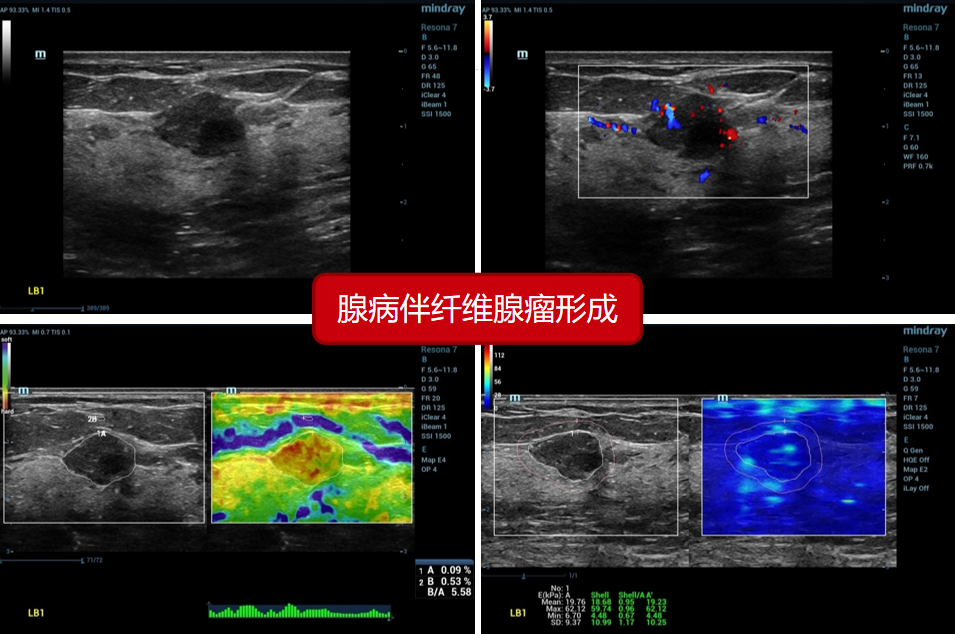

4、甲状腺腺病伴纤维腺瘤形成(昆明医科大第三附属医院):

4、甲状腺腺病伴纤维腺瘤形成(昆明医科大第三附属医院):